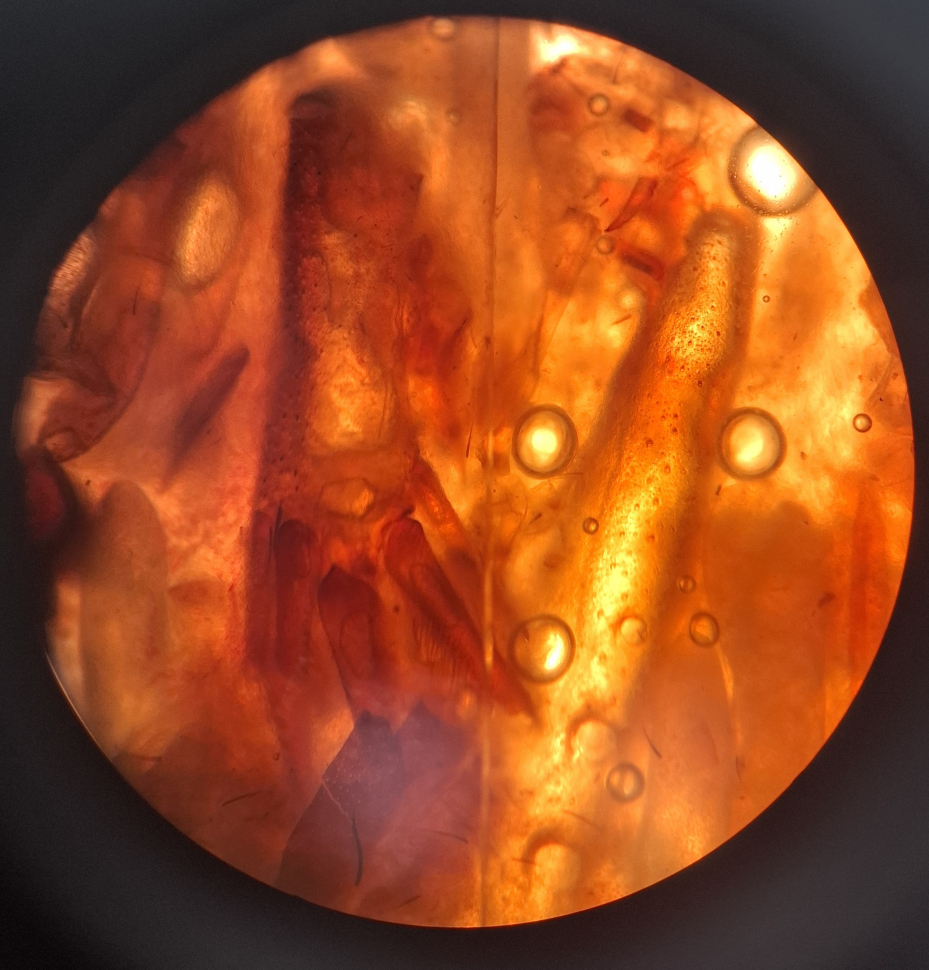

При патологоанатомическом исследовании суриката установлены: увеличение миокарда, кровенаполненность внутренних органов, отёк легких, фибринозные наложения на поверхности печени, увеличение селезёнки, кровоизлияния на слизистой оболочке кишечника. Просвет кишечника плотно заполнен непереварившимися частями корма – фрагментами тела сверчков, непереваренными остатками растительной пищи. Из опроса владельцев установлено, что животное не болело и погибло вскоре после употребления новой партии сверчков – обычной пищи этих животных в неволе.